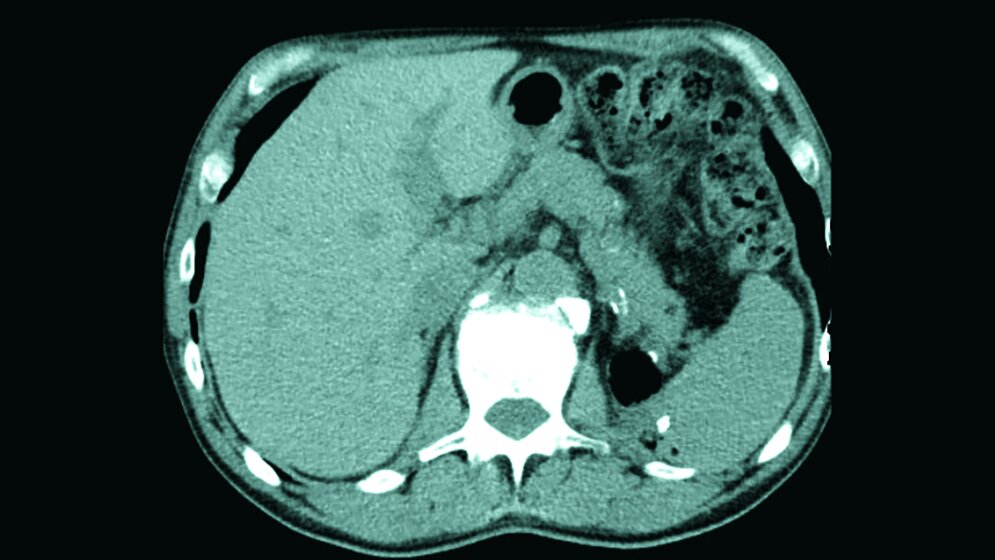

Anomalitäten der Nieren kommen oft vor und sind beim männlichen Geschlecht häufiger anzutreffen als beim weiblichen. Die Beckenniere ist die häufigste Fehllage der Nieren. Sie ist oft asymptomatisch.

Abnormalities of the kidney are common, and are more common in males than females. Pelvic kidney is the most common type of renal ectopia. It’s often clinically asymptomatic.